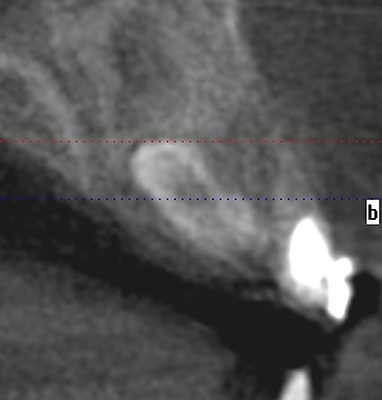

CTにてこのような位置にありました